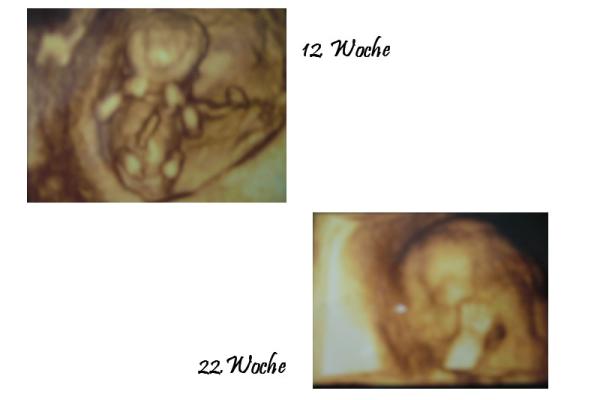

Hey, ich hab hier zwei Stück. Das eine ist allerdings in der 12.Ssw, da ist der Krümel noch ganz und gar drauf. Die Hände wie ein Boxer vorm Gesicht. Das andere ist in der 22.Ssw gemacht worden, da ist nur noch das Gesicht drauf und ein Arm den er davor hällt. Kannst du das erkennen? Mein Krümel ist nun schon 6Monate und wird langsam zum Keks ;o) Liebe Grüße

Dankeschön an euch beide!!! mamanoel, lieb von Dir daß du mir die B ilder zeigst, sind beide sehr süßt, kannman sehr gut erkennen. In der 22. woche sieht man es ja doch schon richtig gut, hätte ich ga rnicht gedacht. Danke Dir SteffiHase, danke für die Meinung, dann werde ich mich jetzt bald erkundigen nach Preisen und wo ich es machen lassen kann. Danke auch Dir!!